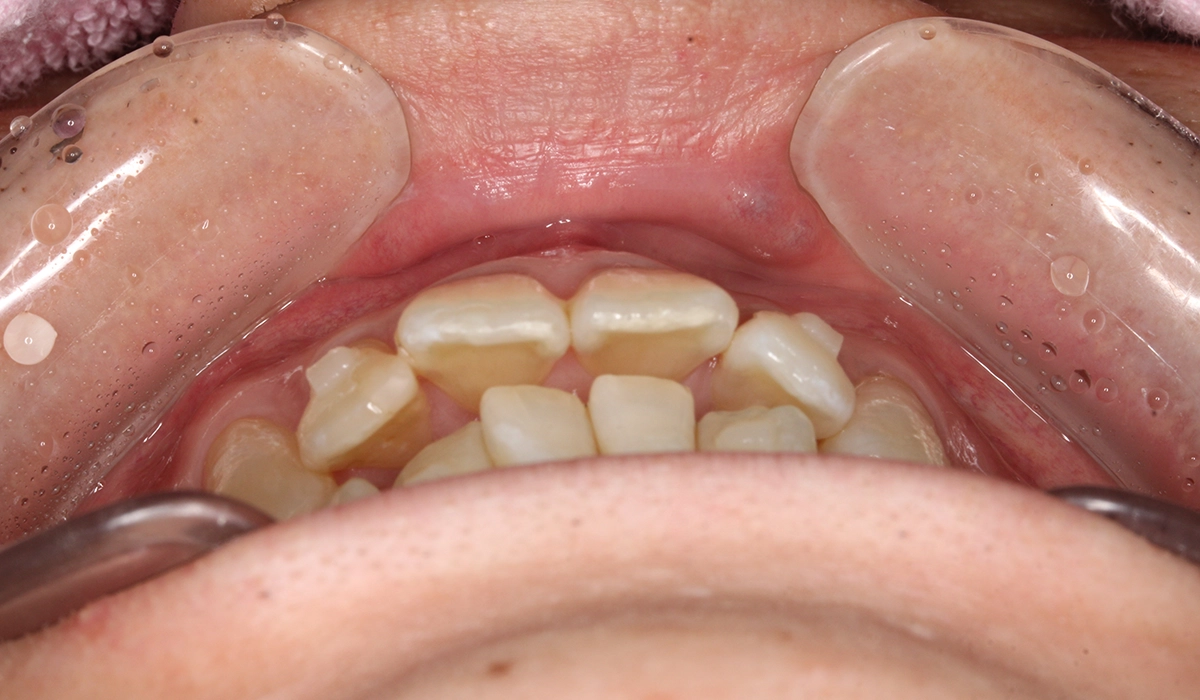

術前:前歯部あおり

術後:前歯部あおり